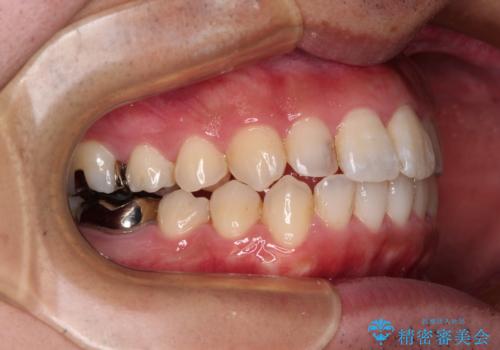

前歯のデコボコと突出感をマウスピース矯正できれいに

- 上下前歯のデコボコと突出感を気にして来院された患者様です。

目立たない装置を希望されたため、インビザラインによるマウスピース矯正を行うこととしました。

矯正治療後に銀歯をセラミックに替えたいとの要望があり、概ね歯列が整ったところで銀歯をセラミックに替え、仕上げにインビザライン1セットを使用して最終的に歯列を整えました。